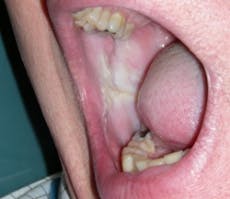

Morsus in Latin means bite. Morsicatio buccarum is biting or chewing of the buccal mucosa; morsicatio labiorum is chewing the lip area (see Figure 2) and morsicatio linguarum is chewing on the borders of the tongue (see Figure 3). The habit may be chewing, biting, or chronic pressure of the tissues. Thicker areas of keratosis may be observed as noted in Figure 3 when the patient continually causes an assault on the oral tissues.